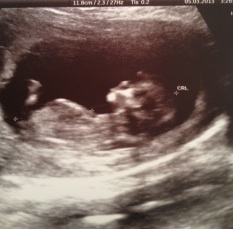

I know it's a bit early, but I'd love some help with guessing!

Girl (although I am not sure that guessing in the 11th week is particularly accurate)!

Thanks for your replies...I know it's hard to tell this early but the nub is so clear I figured I'd give it a shot! Would you say the spine is curved or relatively flat here?

I am far from an expert, but the spine looks moderately flat to me and I think the nub is on the rise. I would "fun guess" a boy. Mostly because of gestation.

Thanks everyone...I was 12 weeks, but the baby measured 11 weeks 5 days. Not sure if that makes a difference or not. Was hoping for a girl!!!

The 11th week is 50/50 as most nubs start out pretty girly looking (like yours) but then if baby is a boy they angle up over the course of the 11th week and sometimes early into the 12th week.

could go either way, but maybe boy since it already has a slight angle? but if it's the same in a week or two, I'd guess girl.